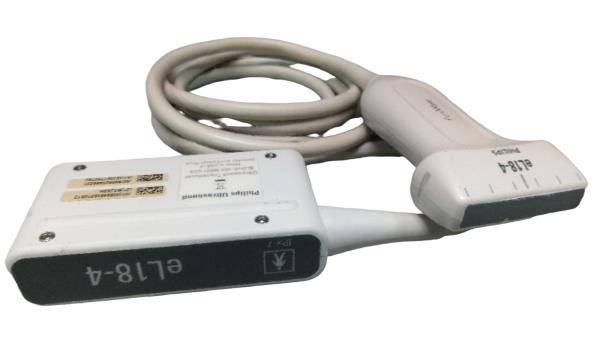

Probe Function: 3.5MHZ convex, abdominal organs

Probe 2: 7.5MHZ Transvaginal probe:gynecologic examination

The Diagnostic Ultrasound Scanner stands out for its exceptional imaging capabilities. Utilizing advanced digital technology, it provides clear and precise images, essential for accurate diagnostics. This scanner is equipped with both convex and transvaginal probes, allowing healthcare professionals to perform a wide range of examinations. Because of this versatile functionality, it greatly enhances the diagnostic process in various medical fields.